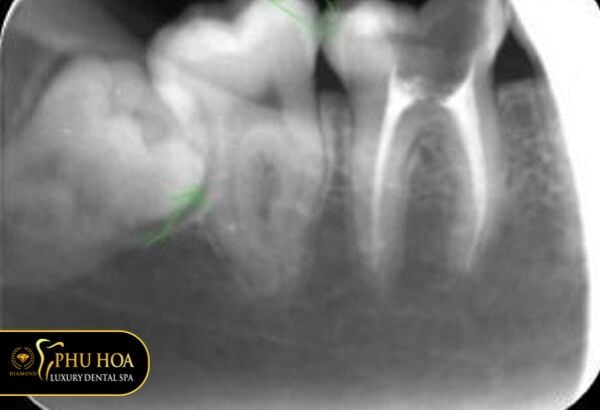

Răng khôn mọc lệch sang răng số 7

Đây là những răng mọc không bình thường, thiếu chỗ. Chính vì vậy chúng thường mọc chen chúc sang răng bên cạnh.

Trường hợp răng lệch sang răng số 7 kế bên nếu không được điều trị sớm có thể gây sâu răng số 7. Bên cạnh đó, có thể làm xô lệch răng hoặc viêm nhiễm răng 7, làm ảnh hưởng khiến răng khó có thể trụ được lâu dài.